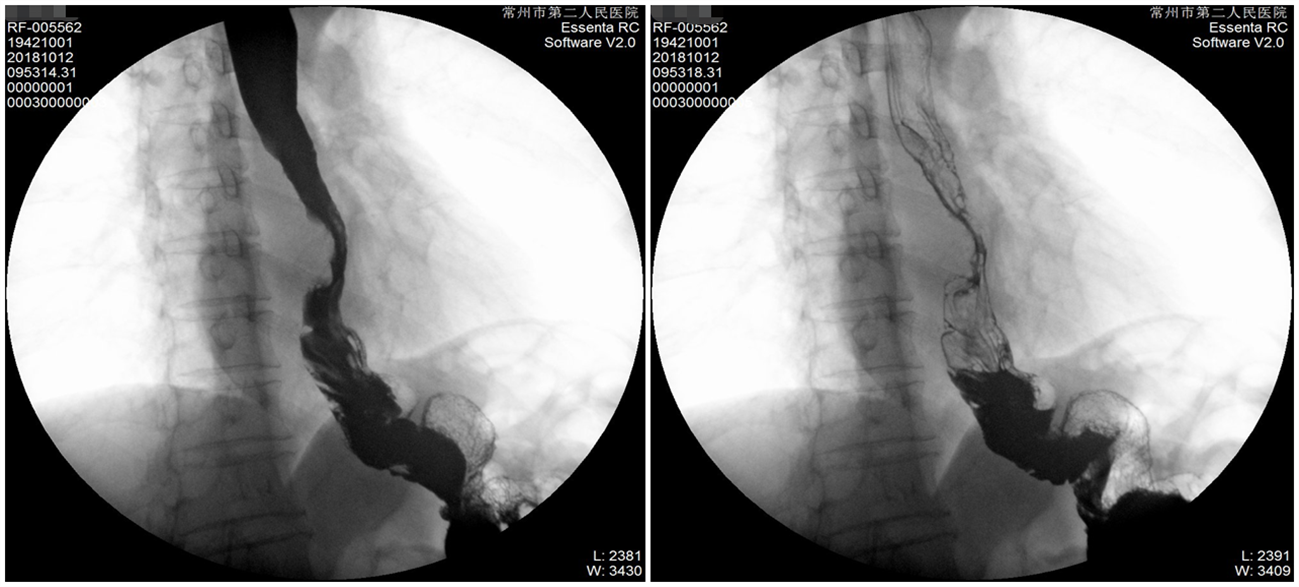

GI(2018-10-12):1、结合病史,考虑为食管中下段MT。2、胃术后改变

2018-10-09 食管中下段管壁增厚